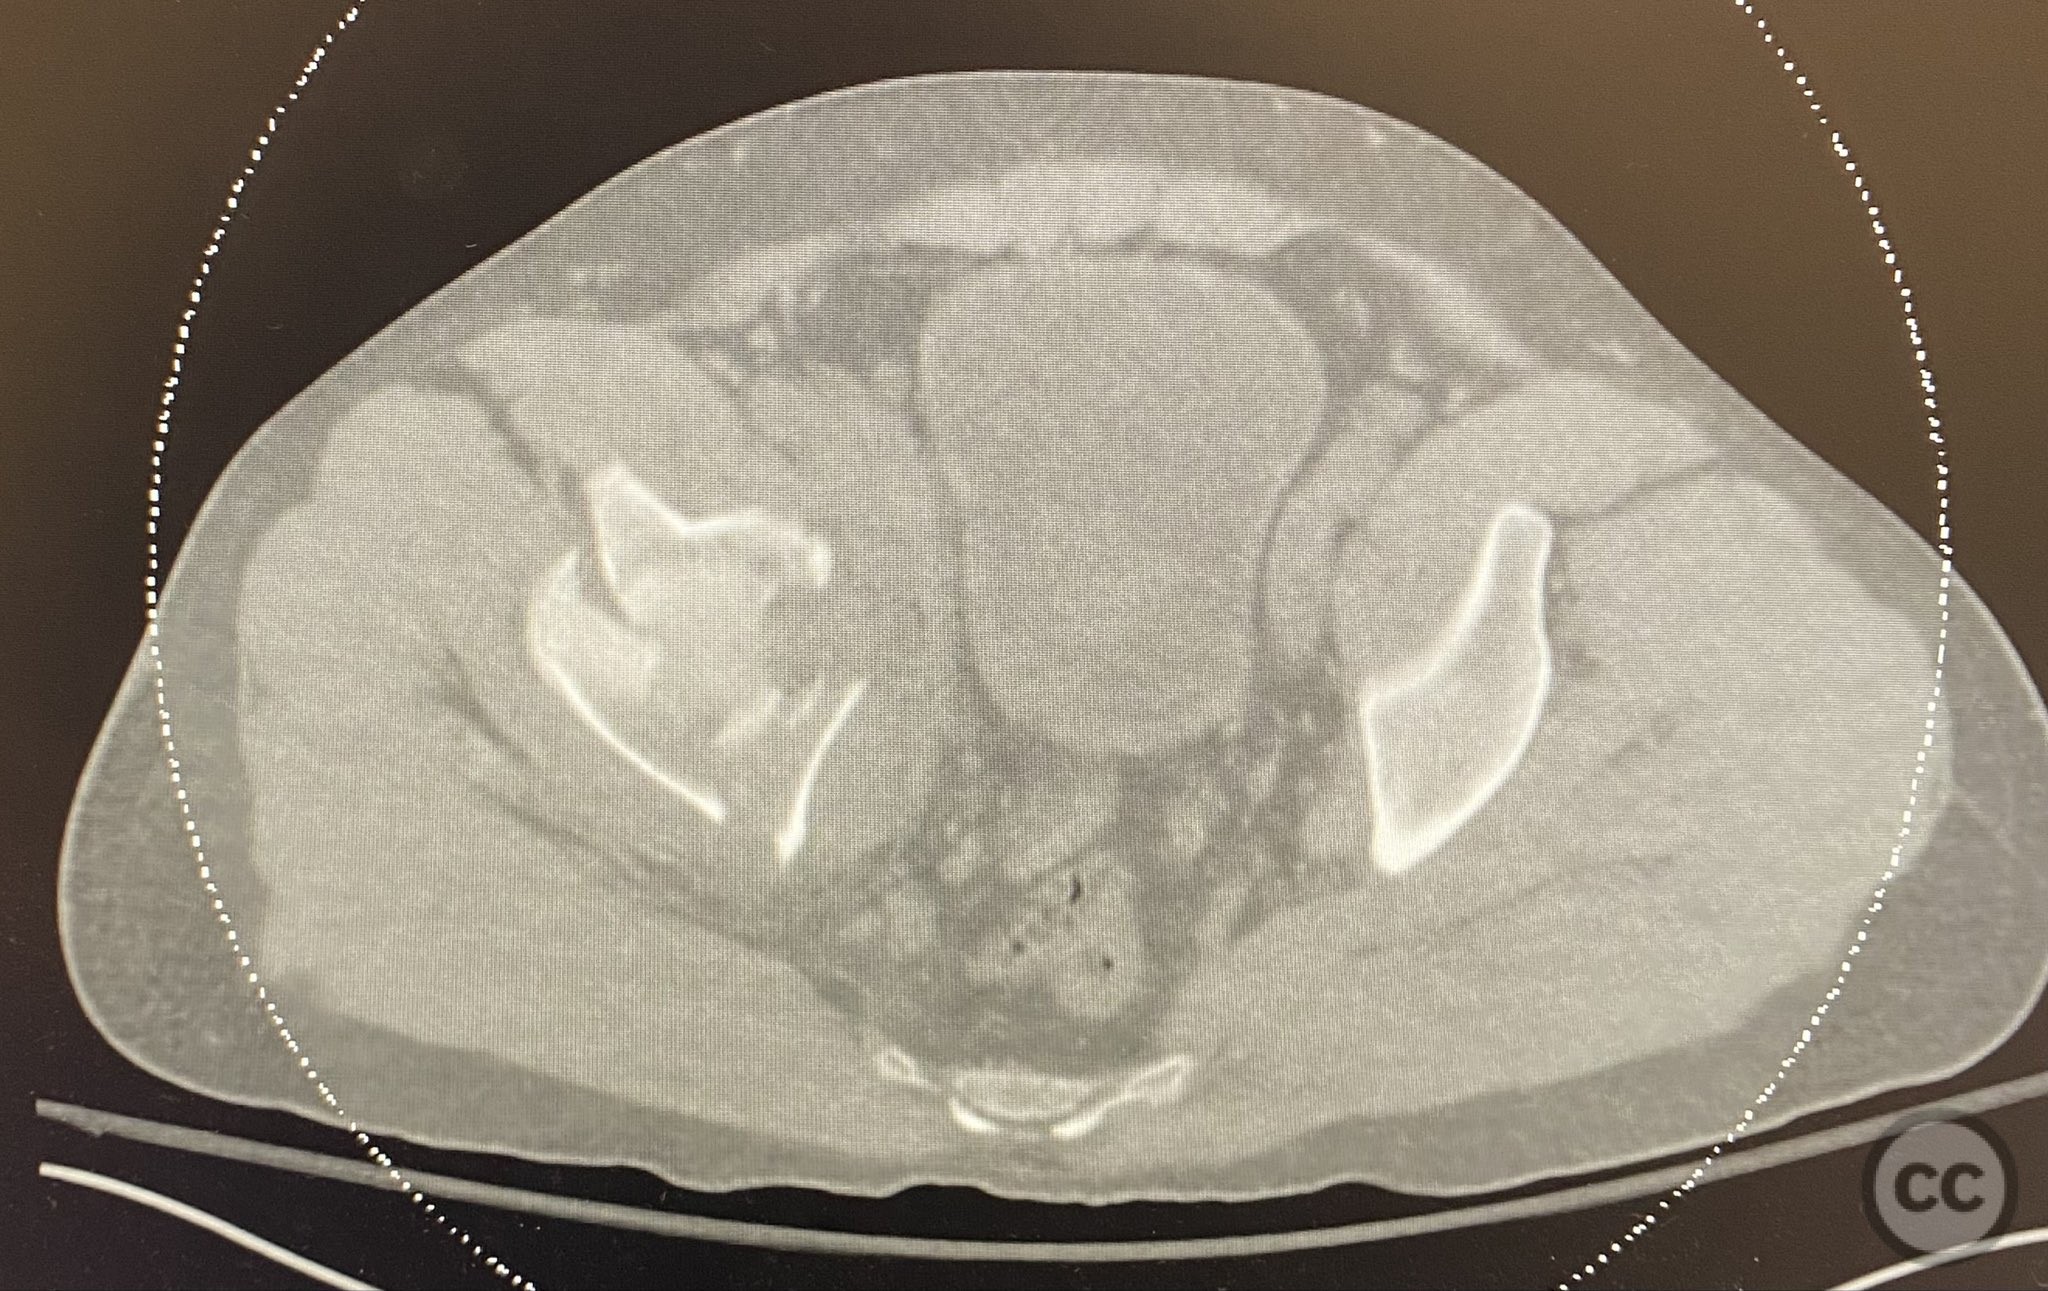

Clinical and radiological findings:  A patient presented with a combined anterior column and posterior hemi-transverse (AC/PHTr) acetabular fracture. Plain radiographs demonstrated multiple displaced fragments involving the acetabular dome and femoral head region, with clear disruption of the anterior column and posterior transverse components. Advanced imaging, including axial and coronal CT, provided detailed visualization of cortical surface displacement, fragment orientation, and associated soft tissue status. The edge of the intact dome and femoral head injuries were identified, as well as a residual defect at the edge of the dome following reduction. AO/OTA classification: 62B2 (anterior column with posterior hemitransverse).

Surface renderings from preoperative imaging facilitated intraoperative correlation between radiographic and fluoroscopic views, aiding in precise interpretation of fragment orientation during reduction. The use of focal plates allowed for maintenance of provisional reductions with bone holding clamps during definitive fixation. Restoration of radiographic lines was confirmed on intraoperative AP fluoroscopy, while postoperative axial CT demonstrated successful central dome repair with a residual edge crush defect at the dome margin.